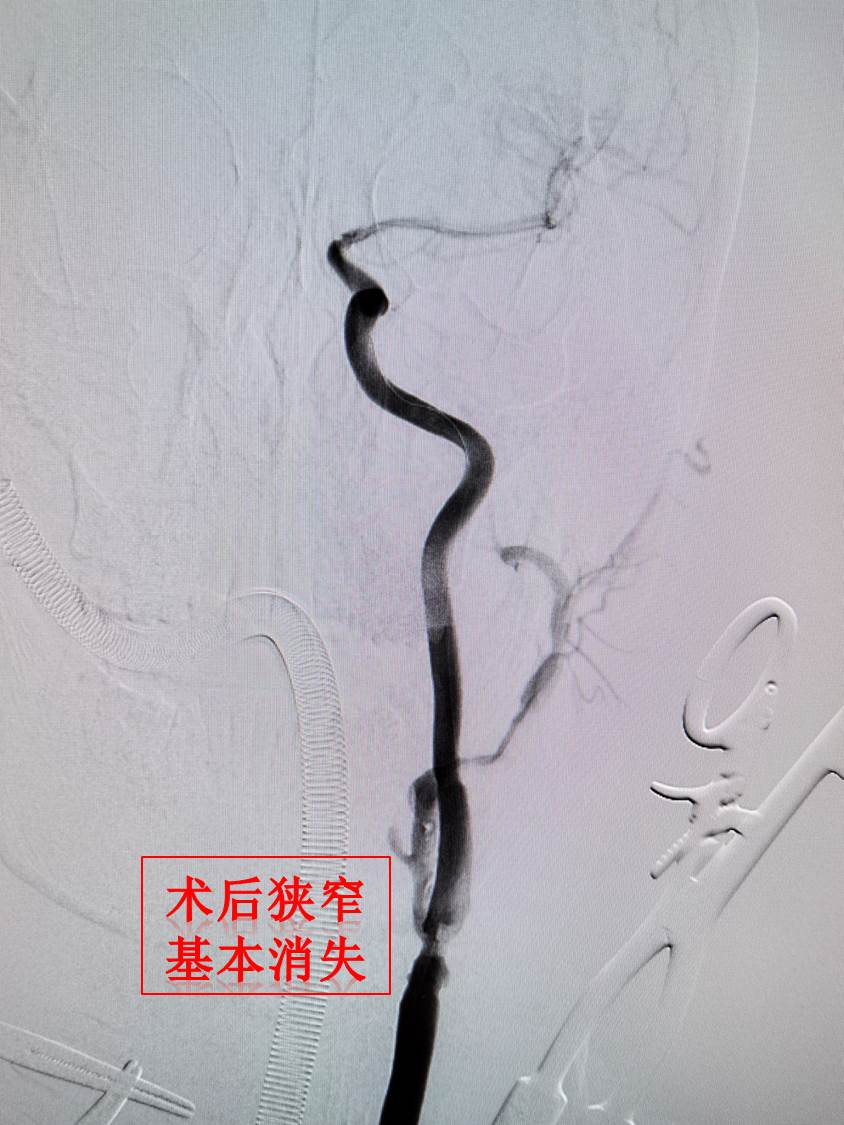

患者术前 CTA 提示左颈动脉重度狭窄有附壁血栓,存在围术期脑梗死风险,且基础疾病多,无法耐受开放手术治疗,存在术后切口感染和创面渗血风险。经血管外科与神经内科脑血管团队严格的术前评估,在韩建峰副院长指导下,血管外科刘建林教授、禄韶英教授、杨林教授、神经内科于嘉教授多学科讨论后,最终决定应用 TCAR 技术规避 CEA 和 TFCAS 技术的不足,为患者进行治疗。并由血管外科杨林教授主刀,在神经内科于嘉教授、血管外科刘超主治医生辅助下,在麻醉科刘畅医师和介入手术室团队的共同协作下,成功完成手术,患者已康复出院。这一技术的临床应用不仅标志着我院在治疗复杂颈动脉疾病的综合技术水平更上一层楼,同时为患者提供了更为安全有效的个性化精准治疗选择。

而 TCAR 技术既有 CAS 的微创特点,又避免了 CEA 的并发症风险,目前国际 RCT 研究证实 TCAR 技术的卒中发生率和心肌梗死并发症均低于传统的 CAS 和 CEA 技术,是目前治疗颈动脉狭窄的最新技术之一。TCAR 是一种结合两种传统治疗方案优点的新兴技术,这种术式显著减少了术后并发症,特别是缺血性脑卒中风险,同时缩短了手术时间(本例手术相比较于传统手术,手术时间减少约 1 小时),进一步提升患者术后的恢复质量,为高风险颈动脉狭窄患者带来全新的、更安全有效的治疗方法。